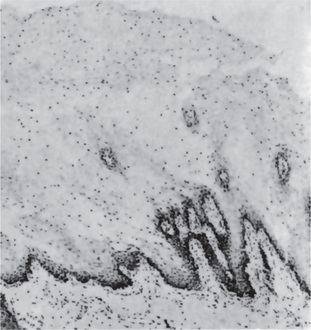

Histopathologic examination of lesional tissue is the most relevant investigation in cases of OLP. Typical findings include hyperparakeratosis or hyperorthokeratosis with thickening of the granular layer, acanthosis with intracellular edema of the spinous cells in some instances, the development of a ‘saw tooth’ appearance of the rete pegs. Band-like subepithelial mononuclear infiltrate consisting of T-cells and histiocytes; increased numbers of intraepithelial T-cells; and degenerating basal keratinocytes that form colloid (Civatte, hyaline, cytoid) bodies, which appear as homogenous eosinophilic globules are consistently seen.

Degeneration of the basal keratinocytes and disruption of the anchoring elements of the epithelial basement membrane and basal keratinocytes (e.g. hemidesmosomes, filaments, fibrils) weakens the epithelial-connective tissue interface. As a result, histologic clefts (i.e. Max-Joseph spaces) may form, and blisters on the oral mucosa (bullous lichen planus) may be seen at clinical examination. B cells and plasma cells are uncommon findings (Fig. 19-5).

Figure 19-5 Oral lichen planus.

(A) Note the basilar degeneration and band-like infiltration of inflammatory cells in the subepithelial zone. (B) Histopathology of lichenoid mucositis (H and E x 100). Note the diffuse infiltration of inflammatory cells involving parts of submucosa. (C) Photomicrograph of Langerhans cells in lichen planus (Gold Chloride staining x400). (D) Photomicrograph of Langerhans cells in lichenoid mucositis (Gold Chloride staining x400) Courtesy of the Dept of Oral Pathology, Ragas Dental College and Hospital, Chennai.